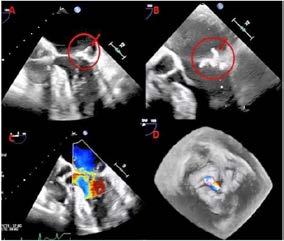

Fibrilación auricular permanente con diagnóstico reciente de angiopatía amiloide cerebral.

Varón de 78 años con antecedentes de diabetes mellitus tipo 2, hipertensión arterial, enfermedad renal crónica (FG 44 mL/min), deterioro cognitivo multidominio y múltiples antecedentes oncológicos urológicos. En marzo 2023, es diagnosticado de fibrilación auricular (FA), tras detectar pulso arrítmico en contexto de bronquitis aguda. Presentaba un riesgo cardioembólico elevado (CHA₂DS₂-VA 4) y se inició anticoagulación con rivaroxabán. En abril 2024, ante un episodio de diplopía binocular, se realizó resonancia magnética cerebral evidenciando la presencia de múltiples microhemorragias y lesiones isquémicas sugestivas de angiopatía amiloide cerebral (AAC).

En octubre de 2024 se realizó, bajo anestesia general, cierre percutáneo de orejuela izquierda mediante acceso femoral derecho, guiado por angiografía y ecocardiografía transesofágica (ETE), y ajustando la dosis de heparina intraprocedimiento de manera estrecha (guiada por TTPA). Se implantó con éxito un dispositivo Amulet 25 mm sin complicaciones. Tras el procedimiento, se suspendió anticoagulación y valorando riesgo-beneficio, se inició antiagregación con clopidogrel, manteniendo control cardiológico y neurológico estrecho.

El paciente evolucionó favorablemente, permaneciendo estable y asintomático desde el punto de vista cardiovascular. Fue dado de alta a las 48 horas, tras confirmar adecuado posicionamiento del dispositivo en ETT. A los 45 días, el ETE de control evidenció el dispositivo de cierre de orejuela izquierda normoposicionado, sin evidenciarse flujos compatibles con leak peridispositivo mediante Doppler color. Se mantuvo el tratamiento con clopidogrel, sin registrar eventos hemorrágicos ni isquémicos posteriores.

En este contexto clínico de alto riesgo hemorrágico, el cierre percutáneo de orejuela izquierda representa una alternativa segura y eficaz para la prevención del ictus. Sin embargo, tras el CPOI, la estrategia antitrombótica óptima a seguir en pacientes con FA no valvular no está completamente definida. Los ensayos clínicos sugieren inicialmente 45 días de anticoagulación más aspirina después del implante percutáneo, seguido de 6 meses de doble antiagregación en pacientes sin fugas significativas alrededor del dispositivo, y posteriormente monoantiagregación. A pesar de esto, la práctica clínica nos enfrenta a individualizar las recomendaciones de práctica clínica teniendo en cuenta el riesgo beneficio de nuestros pacientes.